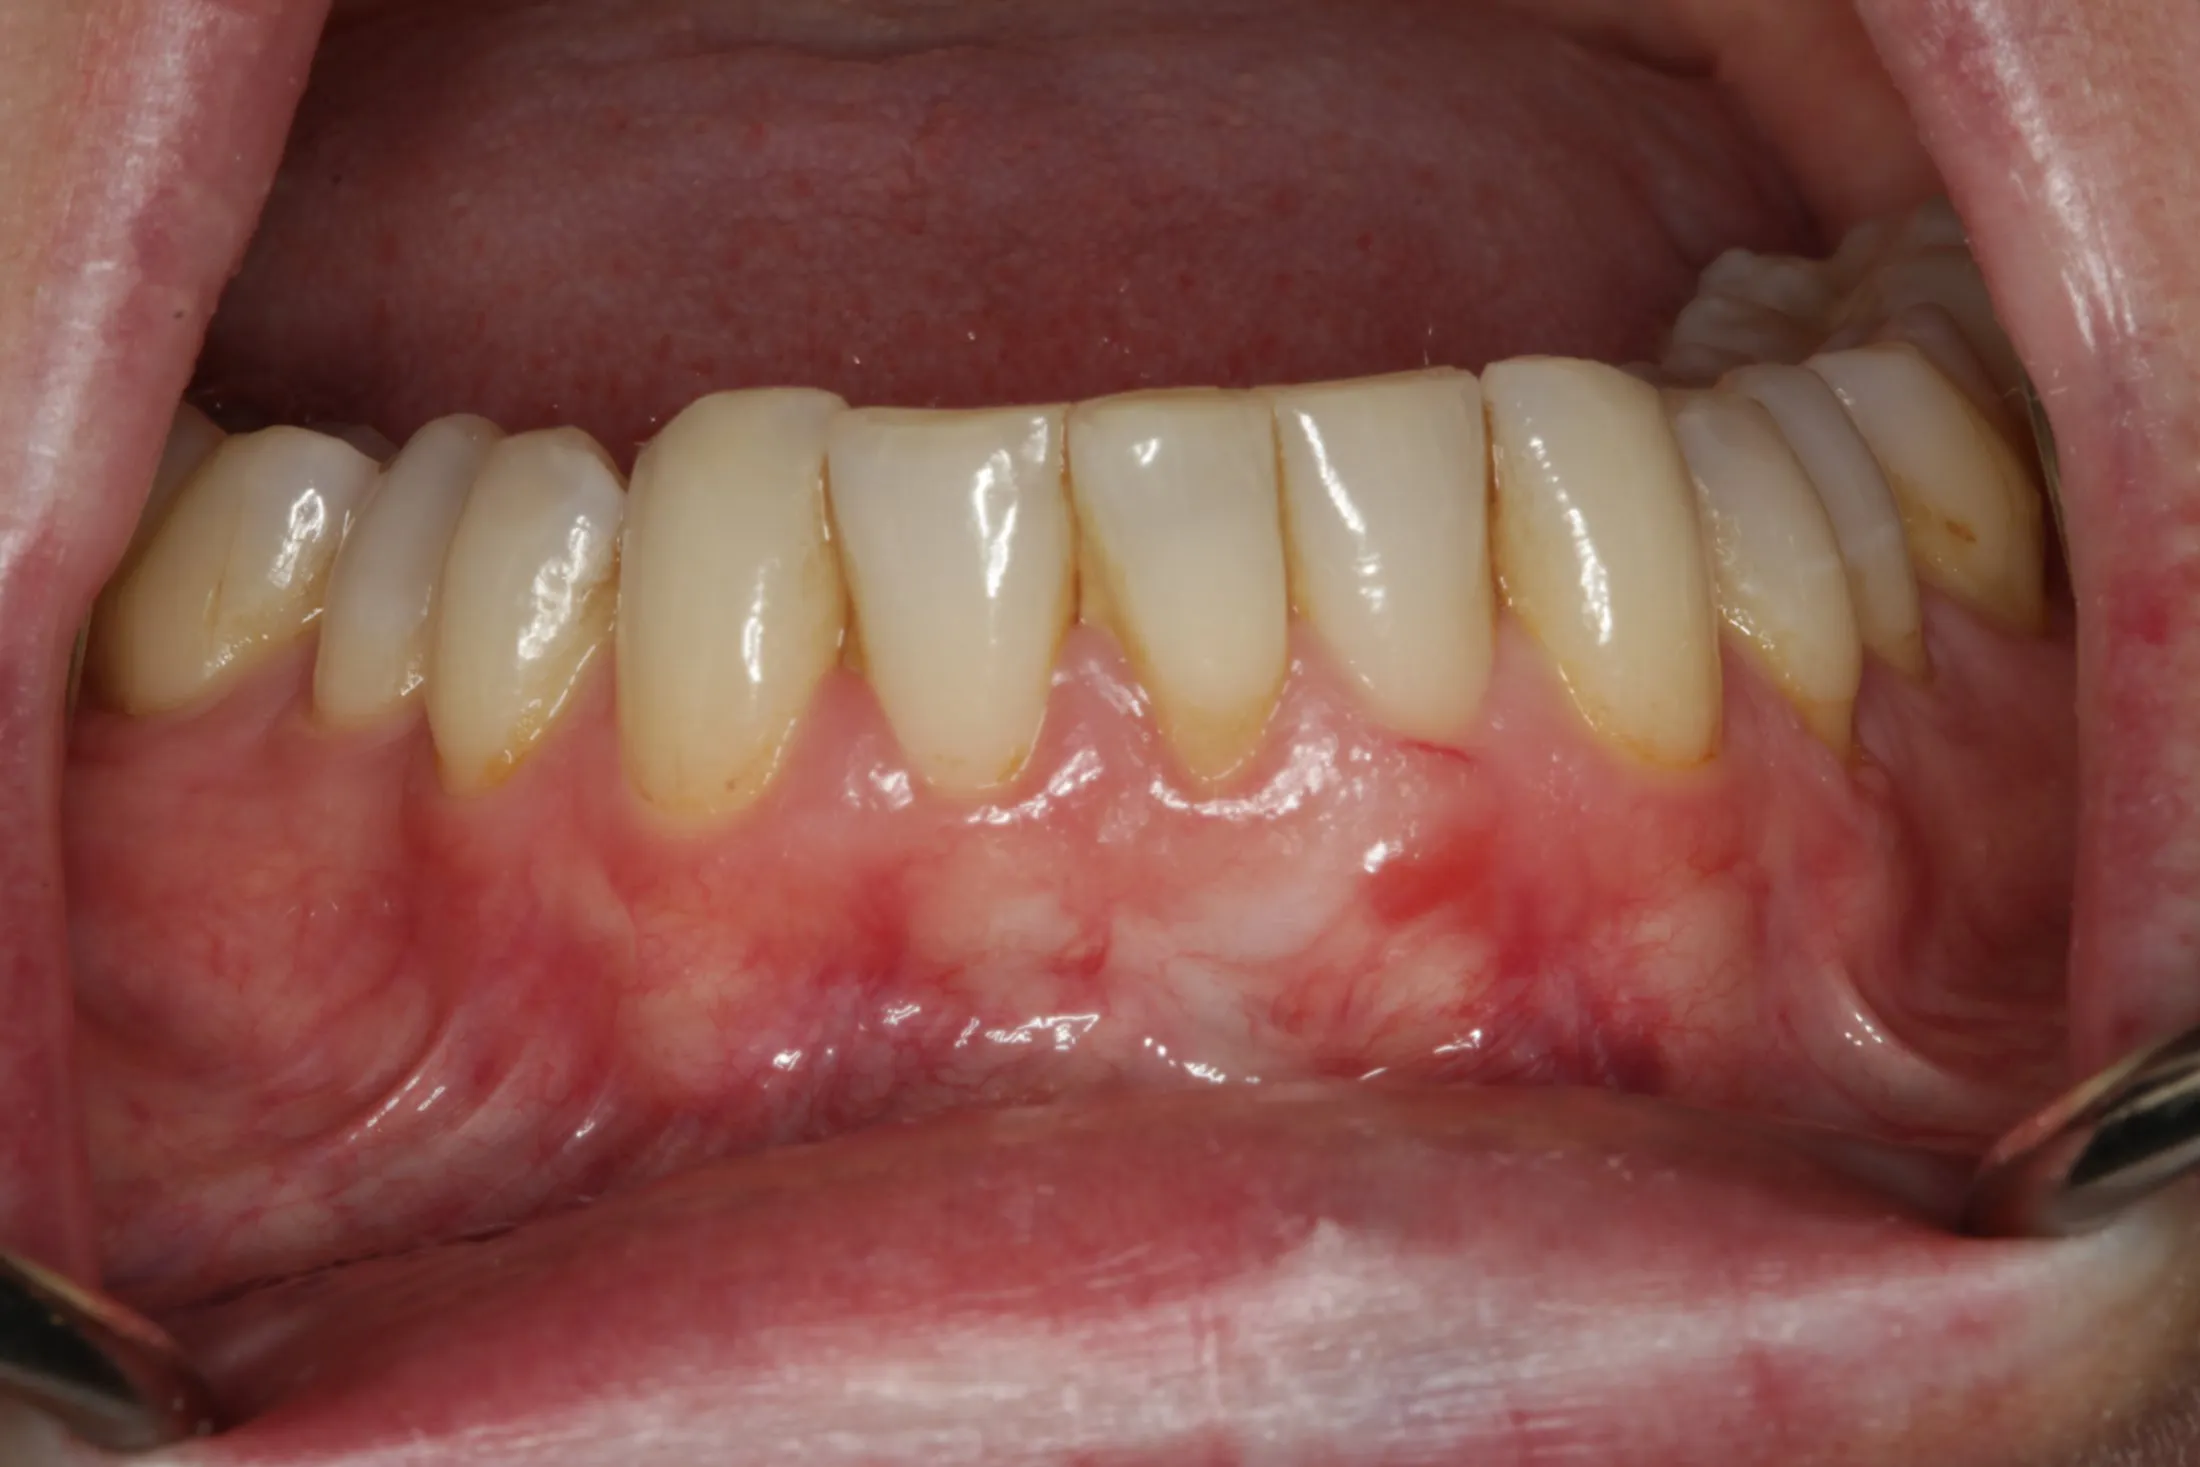

Allograft Dermal with Pinhole Surgery, Alternative to Gum Grafting